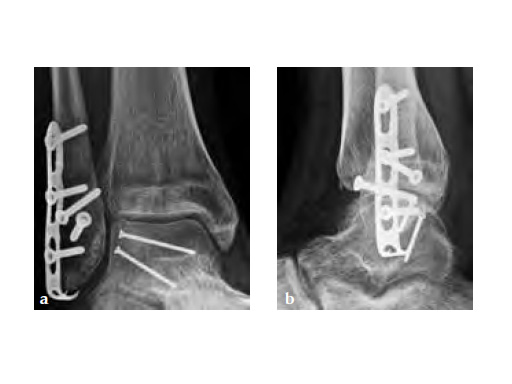

The LCP Hook 3.5 enables tension-band plating with use of 3.5mm screws. The Hook 3.5 was primarily intended for the treatment of simple fractures of the olecranon as well as osteotomies of the olecranon following distal humeral fracture. It has also shown benefits in avulsion fracture of the distal tibia and fibula.

Simple olecranon fractures and osteotomies as well as avulsion fractures of the medial and lateral malleolus treated with traditional tension-band fixation methods are often followed by complications. This is especially evident in patients with poor bone stock and complications include loss of reduction, migration of K-wires and hardware prominence. The LCP Hook 3.5 is a satisfactory alternative fixation.

Fig 3ab X-rays 5 months postoperatively.